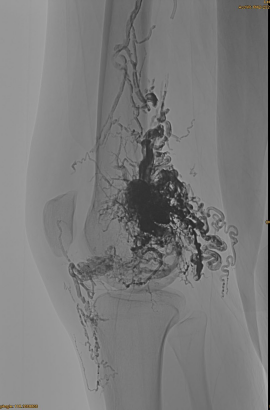

Initial DSA:

Slow Filling Under Roadmap:

Final result:

Hardly any venous outflow:

Late phase, another Embo necessary, but much better: